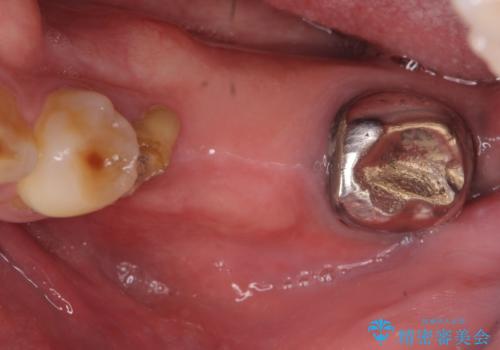

- 左下奥歯が虫歯で抜歯になってしまったため、インプラントにしたいといらっしゃった方の症例です。

欠損部位である左下5、6番目にインプラントを埋入し、オールセラミッククラウンによる補綴を行いました。

左下7番目は再根管治療を行い、オールセラミッククラウンによる補綴を行いました。